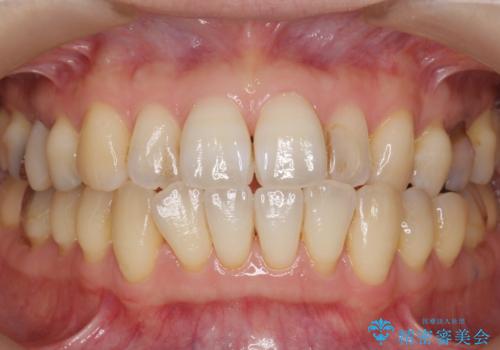

自然な見た目と咬み心地にご満足頂けました。

オフィスホワイトニングを行い、白くなった天然歯に合わせたシェード(お色味)でクラウンを作製しました。